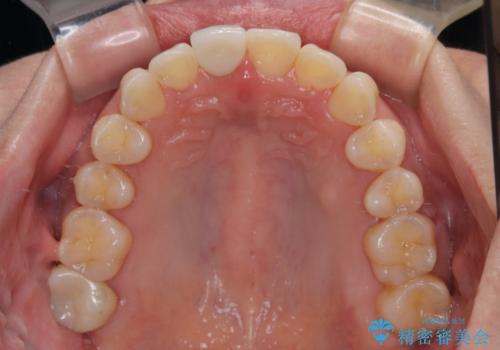

デコボコと乳歯の欠損 ワイヤー矯正とインプラント補綴治療

口元の突出感を気にしているのであれば欠損スペースを利用して抜歯矯正を行うことも可能ですが、横顔の印象はスッキリとしている状態であったため、矯正治療でスペースを閉じきることは不可能と判断し、インプラントによる補綴治療を行うこととしました。

第二小臼歯の欠損によるが乳歯残存や欠損が多く、この乳歯は後続永久歯に比べて幅が非常に大きいため、教聖地料によるスペースクローズが難しいことが一般的です。